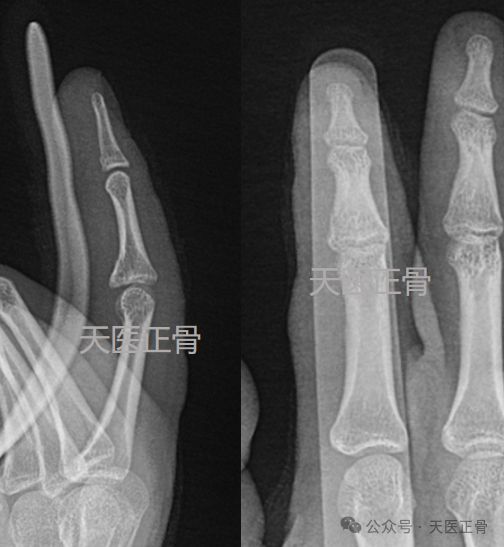

據(jù)Shams報道,遭遇左手哈滕在最近的非移比賽中不幸受傷,經(jīng)過診斷,位性確診為左手遭遇一處小的骨折非移位性骨折,非移位性骨折是預(yù)計指骨折后,斷骨的傷停時間位置沒有發(fā)生明顯的移位,這種骨折通??梢酝ㄟ^保守治療和適當(dāng)?shù)男菹砘謴?fù),對于職業(yè)籃球運動員來說,任何傷病都需要謹(jǐn)慎對待,以確保能夠完全恢復(fù)并重返賽場。